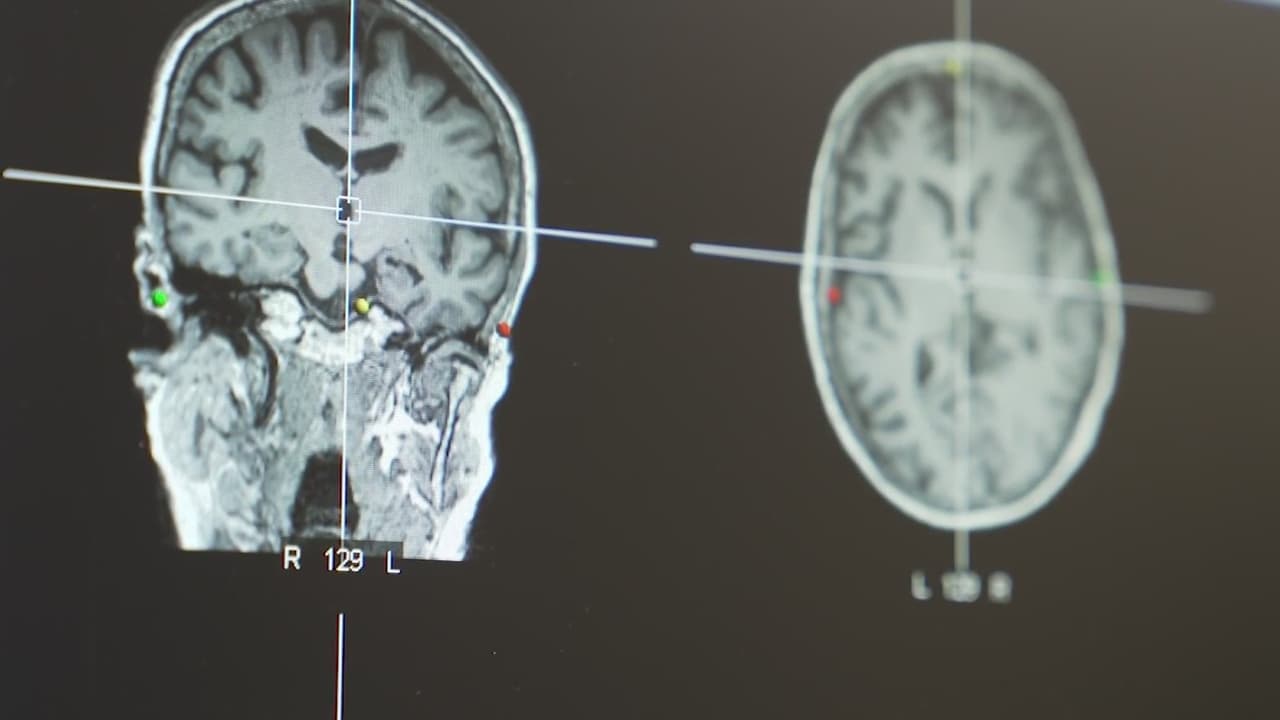

¿Cómo puedes reducir el riesgo de sufrir un derrame?

La Asociación del Corazón de Estados Unidos revela que aunque sólo 10% de los derrames ocurren entre personas menores de 50 años, las cifras van en aumento, por lo que explican cuáles son los síntomas que debes vigilar y cómo reducir el riesgo de sufrir uno.